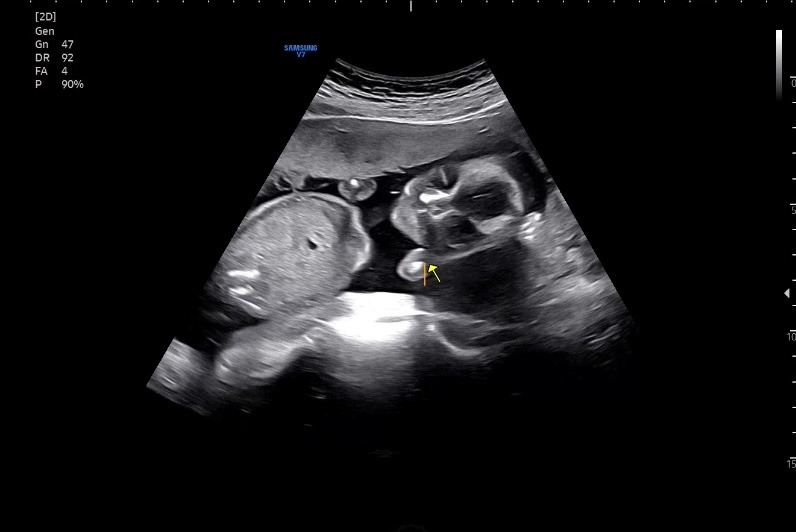

여행 다녀와서 바로 병원에 가봤는데, 건강하게 잘 있었다. 초음파를 보자마자 엄마를 정면으로 보고 있어서 아내는 깜짝 놀랐다고 한다. 우리 딸 여행 재밌었다는 거지???